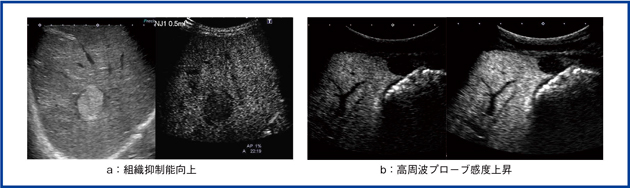

造影超音波の画質は,以前に比べて2つの点で進化している(図1)。1つは,組織抑制能の向上である。従来,高エコーの腫瘤については,バックグラウンドのBモードが邪魔をして造影が難しかったため,CTやMRI検査を補うことが多かった。組織抑制能が向上したことで血管相が良好に診断できるようになった。

もう1つは,近距離の画質改善である。6MHzプローブが高感度化したことで,腫瘍の血流,血管相も良好になり,後血管相(Kupffer相)の抜けが格段に向上した。

図1 組織抑制能向上(a)や高周波プローブ(b)対応など,造影画像の基本性能の向上がある。